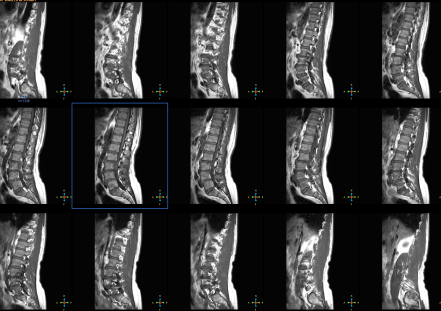

28-MAY-2014  ABDEL-HAKIM WAHEED AL-JOHARY  57 YEARS  EXTRUDED DISC L2-3 WITH LEFT DOWNWARD MIGRATION.

The patient came to the clinic 27-May-2014 complaining of left sciatica with LBP for 3 weeks with pain to above and below the left knee with sudden onset. CT-scan of the lumbar spine done  10-May-2014 showing spondylolisthesis L4-5. MRI lumbar spine done 17-May-2014 showing very huge extruded disc L2-3 with left far downward migration.

MRI showing the huge extrusion of L2-3 with left far downward migration reaching the L3-4 level.

Using image-intensifier, the L2-3 level was identified. Left sided L2-3 hemiflavotomy with hemilaminectomy upper half of L3 was done. The extruded disc was removed far down the axilla in 2 pieces. Foraminotomy of the left L3 root. Left sided cleaning L2-3 disc space.

Smooth postoperative recovery. The power of left foot became normal.